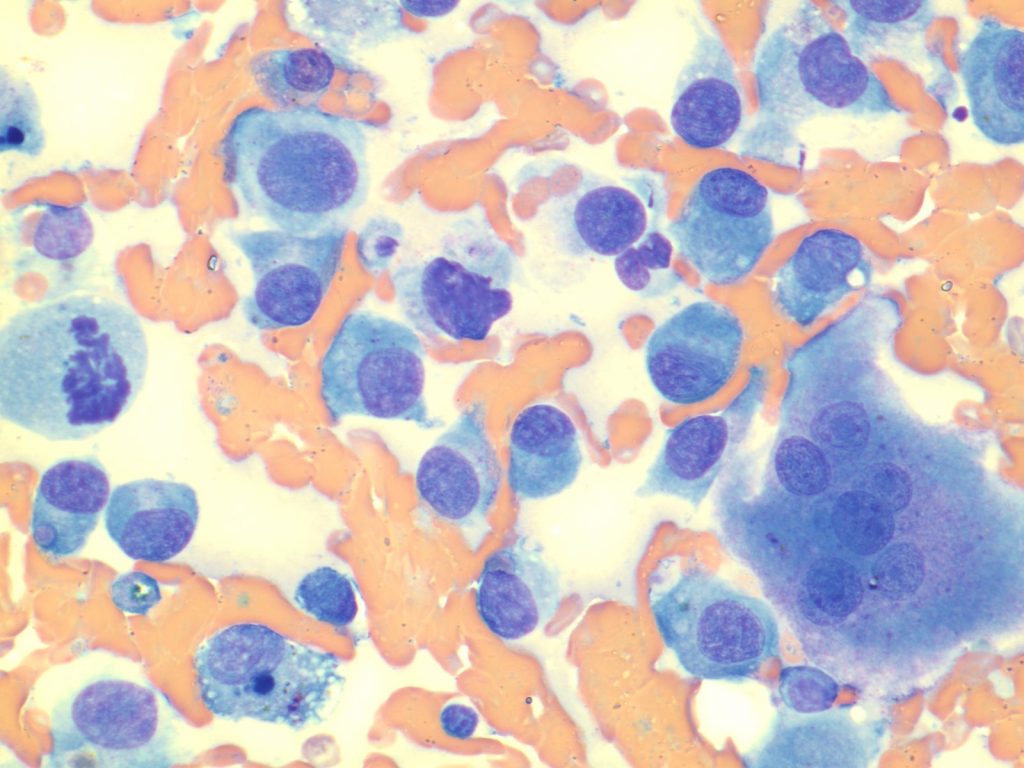

Paciente canino de la raza doberman, macho castrado de 14 meses de edad. Se presenta en consulta después de una cojera intermitente con apoyo de peso, del miembro anterior izquierdo. Presenta dolor y algo de inflamación de consistencia dura en la zona de su radio distal. El dueño ha probado 5 días de carprofeno sin que el perro parezca mejorar su sintomatología por lo que se realizan radiografías de la lesión (FOTO) y posteriormente una punción con aguja de 18G bajo sedación de la lesión ósea (FOTO)

¿Con la anamnesis, tipo de lesión ósea y citología, cual es el diagnóstico de este paciente?